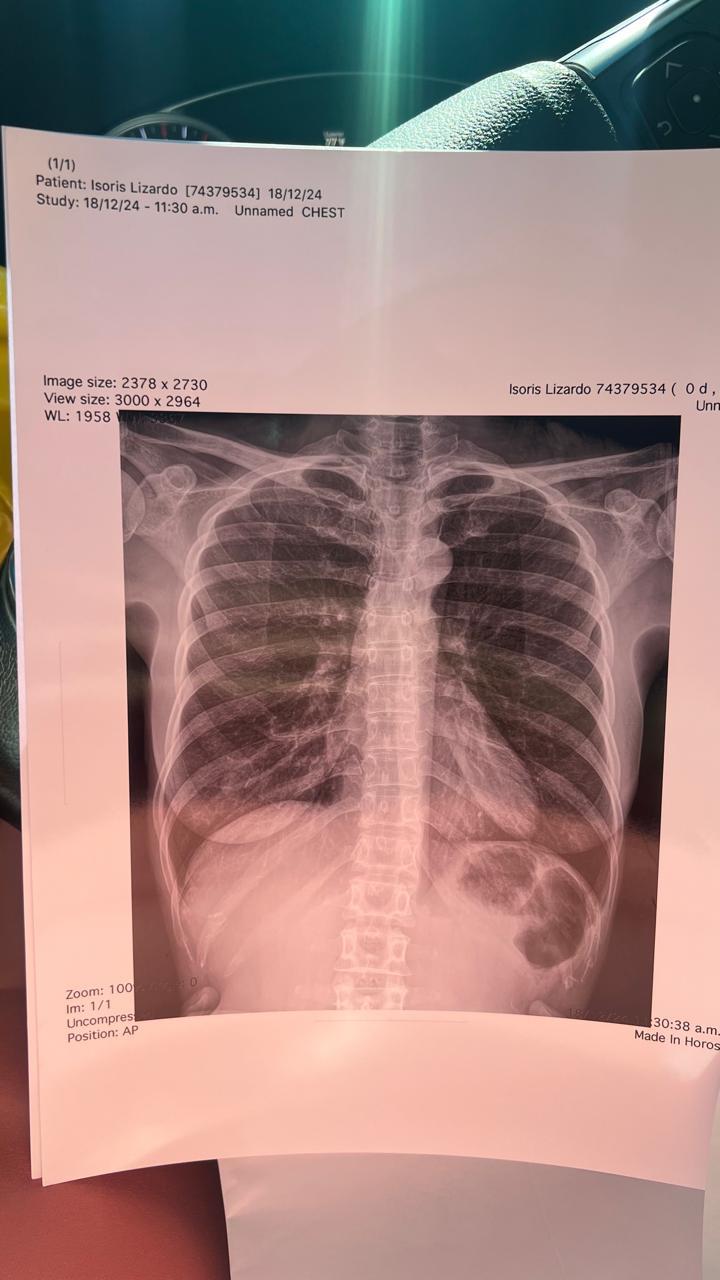

La mujer es identificada como Isoris Lizardo, dijo que fue agredida salvajemente por Guillermo Domingo Dilone. A este, un juez le impuso arresto domiciliario. Por lo tanto, busca la variación a esta medida, ya que teme por su vida.

Detalló que el hombre aprovechó que ella estaba dormida para darle una brutal golpiza que hasta le fracturó varias costillas.